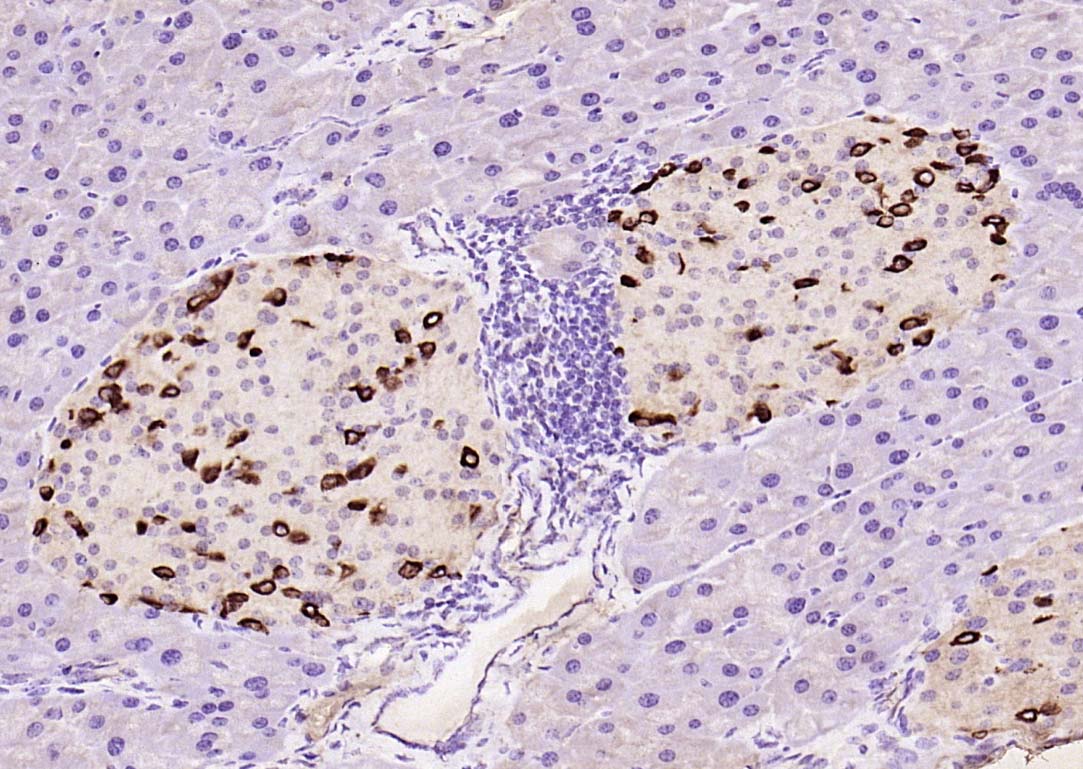

| 英文名称 | GLP-1 (7-36) Rabbit pAb |

| 中文名称 | 胰高血糖素样肽-1抗体 |

| 英文别名 | GCG; GLP 1; glucagon; Glucagon like peptide 1; GRPP; GLP-1(7-36); GLP-1(7-37); Oxyntomodulin; OXM; OXY; GLUC_HUMAN. |

| 产品应用 | IHC-P=1:100-500, IHC-F=1:100-500, IF=1:100-500 Not yet tested in other applications. |

| 交叉反应 | Human, Mouse, Rat (Pig, Cow, Sheep) |

| 组织特异性 | Glucagon is secreted in the A cells of the islets of Langerhans. GLP-1, GLP-2, oxyntomodulin and glicentin are secreted from enteroendocrine cells throughout the gastrointestinal tract. GLP1 and GLP2 are also secreted in selected neurons in the brain. |

| {IHC-P} | {1:100-500} |

| {IHC-F} | {1:100-500} |

| {IF} | {1:100-500} |